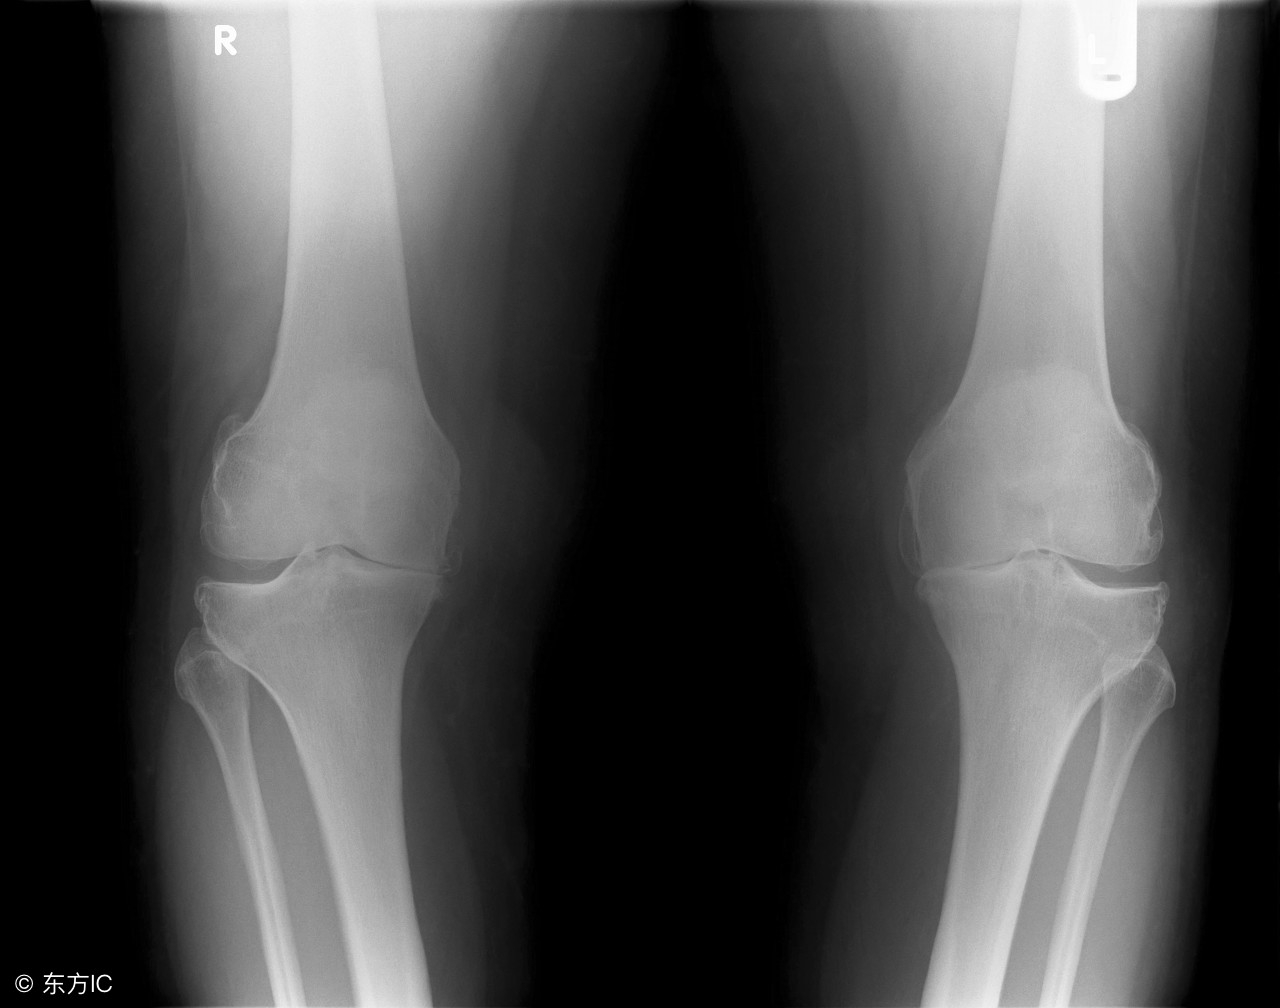

首先,我们来了解一下什么是骨刺?骨刺,也称为骨质增生,它是骨骼的一种存在状态,是骨骼生长发育退变过程中的一种表现形式,就像是我们的“白头发”,是客观存在的。骨质增生的表现形式多种多样,因部位不同而各有特点,椎体边缘表现为“唇样”,后期可以连接两个椎体形成“骨桥”,而在小关节则表现为“变尖”。随着年龄的增长,一般到35岁以后椎体间的椎间盘就退化变薄,椎体周围原有的肌肉、韧带、关节囊的生理平衡遭到破坏。机体为了适应这些变化,重新建立新的平衡,就在椎体的边缘生长出了新的骨骼以增加骨关节的稳定性,它可以增加骨关节的接触面积,减少单位面积受到的压力,从某种意义来讲骨质增生是机体的保护性反应,是人体的一种代偿性反应,属正常的生理退变现象。

其次,我们要有正确对待骨刺的思路。由于骨质增生是人体衰老的自然现象,只有当骨质增生引起了局部组织充血、水肿、炎症和粘连以及因此而压迫或刺激神经和血管引起的一系列症状和体征时,才有必要进行治疗。经过大量的、长期的观察和研究,骨质增生的程度与临床症状之间缺乏必然的联系,说明增生的骨质只有在特殊的情况下才能引起临床症状,也就是说,有骨刺是常见的,由骨刺导致临床症状和表现的是非常少的。